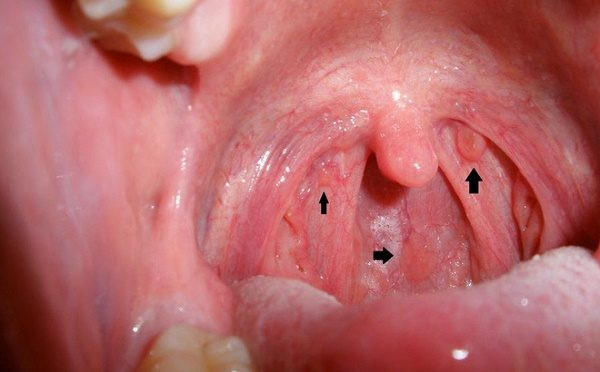

Tôi tin rằng đối với nhiều người, virus HPV còn tương đối xa lạ, nó thường ảnh hưởng đến cổ tử cung của chúng ta và dễ gây ung thư, nhưng bạn có biết không? Trên thực tế, nó vẫn là mối nguy hại lớn đối với khoang miệng của chúng ta.